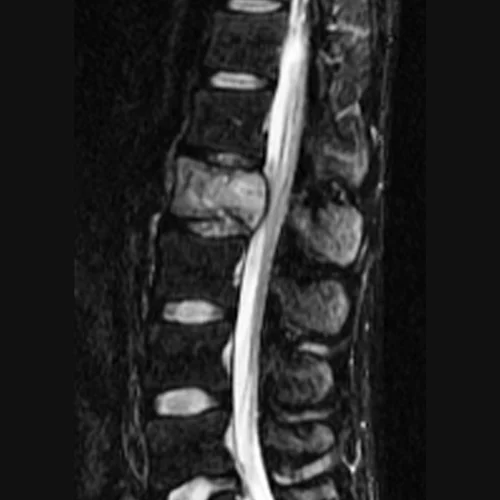

Peripheral Nerve Tumors

Homepage Peripheral Nerve Tumors